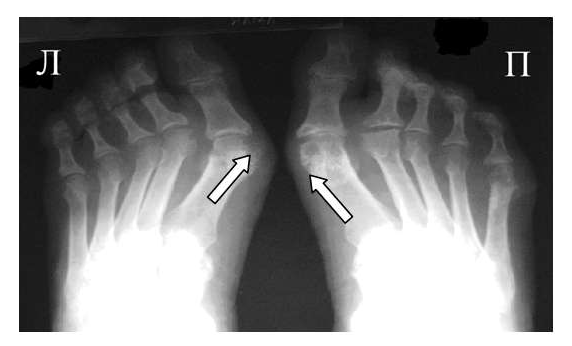

Одним из главных отличительных признаков ревматоидного артрита (РА) от других заболеваний является симметричность изменений мелких суставах кистей и стоп, которые становятся суставами-«мишенями» в первую очередь и поэтому именно эти области изучаются для определения стадии заболевания. Наиболее часто используемой в повседневной практике рентгенологической классификацией является деление ревматоидного артрита на стадии по Steinbrocker в различных модификациях.

Рис. 3 Сочетание ревматоидного артрита и остеоартроза

Большинство ошибок встречаются при начальных стадиях, особенно при начале РА в пожилом возрасте и сочетании его с остеоартрозом (см. рис. 3). В этом случае для подтверждения диагноза РА и предупреждению случаев его гипердиагностики служит выявление симметричных эрозий в типичных для ревматоидного артрита суставах (запястья, плюснефаланговые, пястно-фаланговые).

Рис. 4. Изменения кистей при ревматоидном артрите (а остеопороз, бсужение суставных щелей, в кистовидные просветвления, г костные эрозии, д анкилозирование)

Необходимо также помнить, что, как правило, при РА эрозии не предшествуют околосуставному остеопорозу, кистам и сужению суставных щелей. Имеет место последовательность развития стадий РА (см. рис. 4), в отличие от эрозивных артритов другого генеза (псориатического, серонегативного)